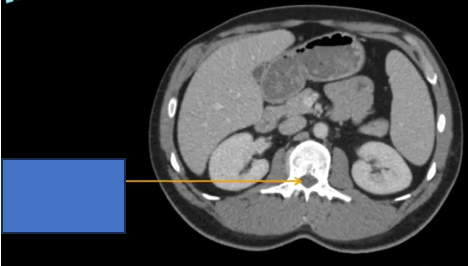

cq trong hình ?